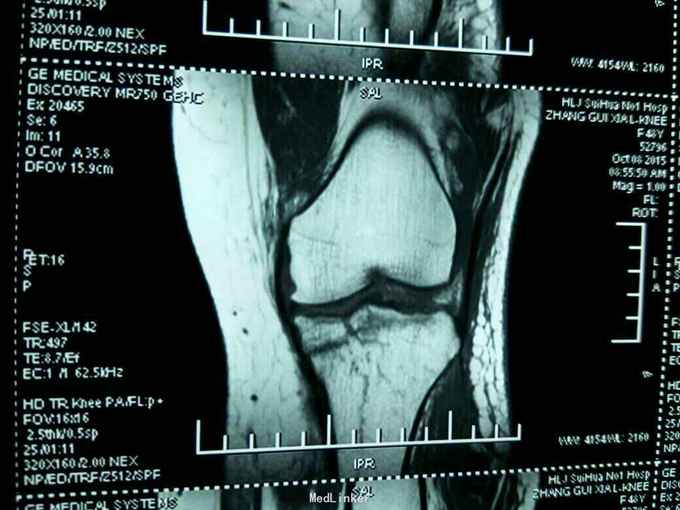

患者女性,48岁。因摔伤左膝关节,肿胀,畸形,活动受限二小时来诊。病人于二小时前滑倒摔伤,当即左膝关节肿胀畸形,局部肿胀,不敢下地行走。门诊拍片示:左膝关节胫骨平台塌陷骨折。以:左胫骨平台塌陷骨折收入院。

左膝关节局部肿胀,局部压痛。浮髌试验阳性。膝关节屈伸活动受限。不能下地行走。侧方应力实验阴性。抽屉实验阴性。拍片示:左胫骨平台骨折。核磁共振示:左胫骨平台塌陷骨折。局部骨质塌陷约1cm